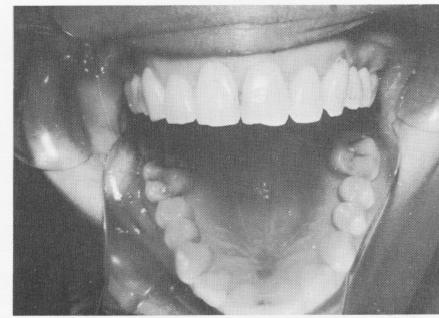

Fig. 8-16. The restorations as they appeared in the mouth.

6 Clinical view of upper endosseous implant restoration